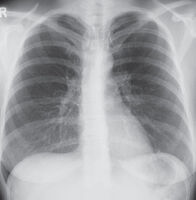

Konventionelles Röntgen

Die Röntgenuntersuchung steht für viele Fragestellungen auch heute noch an erster Stelle, weil sie einfach durchzuführen ist, eine relativ geringe Strahlenbelastung hat und einen schnellen Überblick über größere Körperabschnitte ermöglicht. Eine Röntgenröhre erzeugt Röntgenstrahlen, die die verschiedenen Gewebe des Menschen in unterschiedlichem Ausmaß durchdringen. Die Röntgenstrahlen treffen auf einen Detektor, der sie direkt in elektrische Impulse umwandelt („digitale“ Radiographie). Gegenüber den heute veralteten Röntgenfilmen hat ein digitales Röntgenbild den Vorteil, an vielen Bildschirmen gleichzeitig betrachtet, auf Massenspeichern archiviert und über Datenleitungen verschickt werden zu können.

Für die einzelnen Zentren der Kerckhoff-Klinik sind die wichtigsten Fragestellungen für die konventionelle Röntgenuntersuchung:

• Herzzentrum

Die wichtigsten Fragen der Kardiolog:innen und Herzchirurg:innen an den Radiologen betreffen Vergrößerungen der Herzkammern,  Einlagerung von Flüssigkeit um die Gefäße und Bronchien und die Entwicklung von Pleuraergüssen. Wichtige Begleiterkrankungen sind Entzündungen und Tumore. In der postoperativen Kontrolle nach Herzoperationen sind vor allem Komplikationen wie Entzündungen, Blutungen und Lufteintritt in das Rippenfell („Pneumothorax“) auszuschließen.